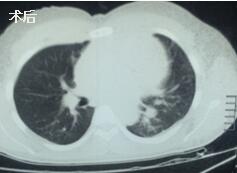

當看到病人癥狀緩解,復(fù)查胸部CT幾近完美,我們那種自豪感油然而生。偶爾去治愈,常常去幫助,總是去安慰,我們深知,小伙子的人生之路并不長,只能深深祈禱他在我們的治療下能走得更遠一些,能把剩下的日子走的更充實一些。而我們在能夠幫助人的時候,別一味地去安慰,永不言棄,是我們這一群胸外人堅貞的信念。